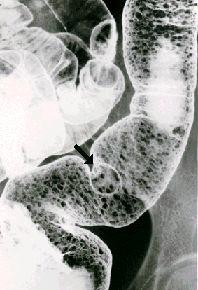

小さな進行性大腸癌を伴った密生型の家族性大腸ポリポーシス(大腸腺腫症)の注腸X線写真  S状結腸~下行結腸のX線写真。5ミリ以下のポリープがびまん性に密生しています。これらの無数のポリープの中に、14ミリ大の結節状の腫瘍(矢印)が、認められます。その中央部は陥没しています。小さな限局潰瘍型(Borrmann2型)で固有筋層に浸潤しての進行癌でした。

疾患(病理主体)の分類大腸腺腫症(家族性大腸ポリポーシス・Gardner症候群)/

部位(臓器別)大腸/S状

腫瘍の肉眼分類2型(潰瘍限局型)/

病変の最大径(ミリ)10〜14

腫瘍の深達度mp